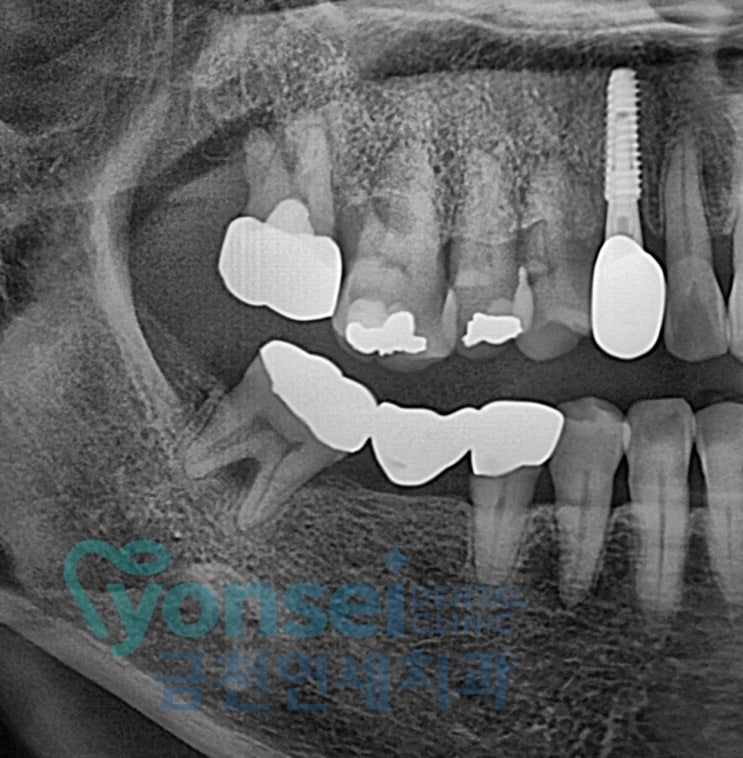

치주염으로 인한 발치와 임플란트 과정

안녕하세요 금천연세치과 송찬호 원장입니다. 오늘은 많은 분들이 궁금해하시는 치주염으로 인한 치아발치...